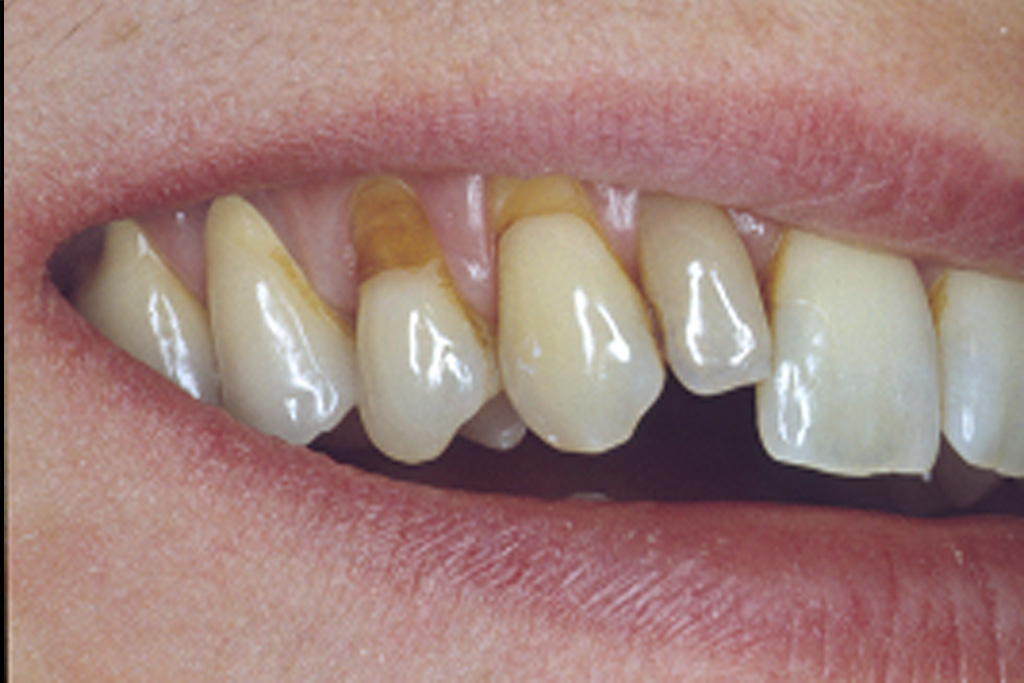

Die präzise Darstellung präparierter Zahnstümpfe auf dem zahntechnischen Meistermodell stellt auch heute noch eine der wichtigsten Schnittstellen zwischen Zahnarzt und Zahntechniker dar. In der Produktionskette hin zur fertigen Krone nimmt dabei der Zahnarzt eine entscheidende Schlüsselstellung ein. Nur er kann durch seine reproduzierbare und präzise Abformmethodik die Voraussetzung für ein perfektes Modell schaffen und damit Passungenauigkeiten der anzufertigenden Krone vermeiden. Dies ist besonders deshalb wichtig, weil Passungenauigkeiten an Kronenrestaurationen (Über- und Unterextension des Kronenrandes, übergroßer Randspalt ) häufig eine Fülle perioprothetischer und ästhetischer Probleme verursachen (Abb.1 ) :

Da die Präparationsgrenze bzw. der Präparationsrand in der Regel 0,5 bis 1,5 mm unterhalb des Zahnfleischrandes (= subgingival ) verläuft, wird zumeist während der Präparation des Zahnes das Zahnfleisch verletzt. In der Folge tritt eine verstärkte Blutung am Zahnfleischrand (= Sulkus) auf.

Bei der anschließenden Abformung der präparierten Zahnstümpfe bestehen zwei Probleme (Abb2.) . Zum Einen muss das den Zahn umgebende Weichgewebe vom Präparationsrand abgedrängt werden (= Retraktion) und zum Anderen darf während der Abformung kein Blut auf die abzuformende Zahnoberfläche gelangen. Unzureichende Retraktion und Blutungen im Sulkus verhindern eine präzise Abformung. Die Abformung muss wiederholt werden.

Mit Hilfe des Lasers können heute erstmals diese beiden. Hauptprobleme bestmöglich in den Griff bekommen werden.

Der Laser verdampft punktuell störende Gewebeanteile im Sulkus und stoppt gleichzeitig durch seine blutungsstillende Wirkung die Gewebeblutung . Dabei ist die Gewebeschädigung (=Trauma) minimal. Durch diese minimaltraumatisierende Wirkung ist die anschließende Wundheilung wesentlich schmerzärmer als bei der früher üblichen elektrochirurgischen Abtragung. Im Zuge der Heilung ist die Schrumpfungstendenz des Zahnfleischrandes zudem erheblich geringer. Dies fördert das ästhetische Erscheinungsbild der eingegliederten Krone im Zahnhalsbereich, da der Kronenrandbereich unterhalb des Zahnfleischrandes verbleibt (Abb. 3 ).

im Bereich der Vollkeramikkronen an den Oberkieferfrontzähnen 13-23